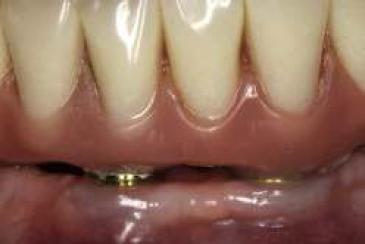

Luego de un tiempo de recuperación para la paciente (30 min aproximadamente) se retiraron los cilindros de protección y se instalaron los transfer (fig. 9), se realizó entramado con seda dental entre ellos y se ferulizaron con acrílico en estado arenoso con método de goteo (Duralay®, Reliance Dental Mfg. Co., Worth, IL, EE. UU.) (fig. 10). Nuevamente se probó la inserción y posicionamiento de la guía en boca, para que esta no interfiriese con los transfer o el acrílico. Se comprobó la correcta oclusión con la arcada antagonista.

Al tercer día se realizó la instalación con torque manual y ajuste oclusal (figs. 13,14,15,16).

A los 10 días, luego de la cirugía, se citó a la paciente a control para realizar la retirada de la sutura11; se dio torque a los tornillos protésicos (10 N/cm) y se chequeó la oclusión nuevamente. Se ha seguido controlando a la paciente cada 6 meses, hasta cumplir 2 años desde la fecha de instalación de la aparatología, sin manifestar complicación alguna (figs. 17, 18, 19, 20, 21).